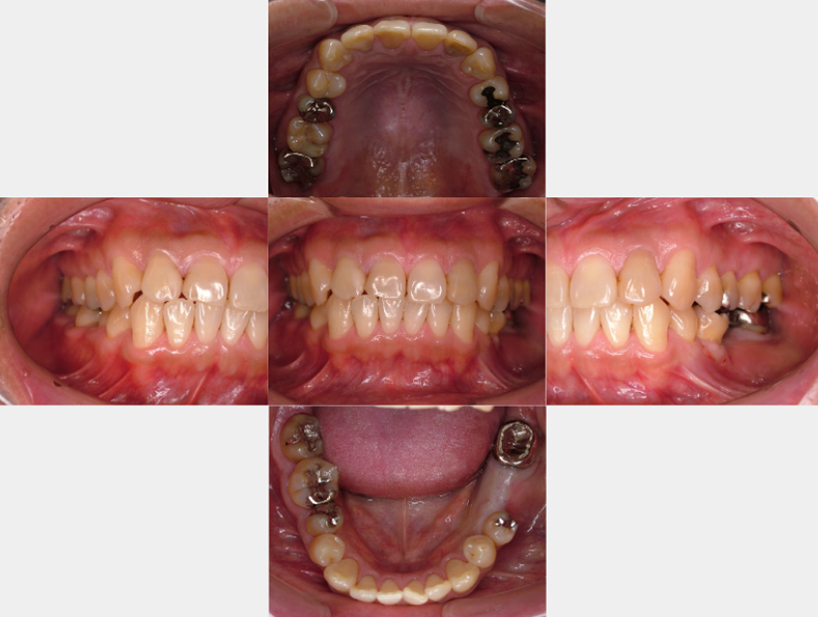

治療前治療後

| 治療内容 | インプラント奥歯1本・根管治療6歯 |

|---|---|

| 患者様の年齢 | 54歳 |

| 患者様の性別 | 女性 |

| 治療期間 | 2年 |

| 治療回数 | 根管治療合わせて70回程度 |

| 治療費用 | インプラント1歯 50万円/根管治療6歯 30万円 |